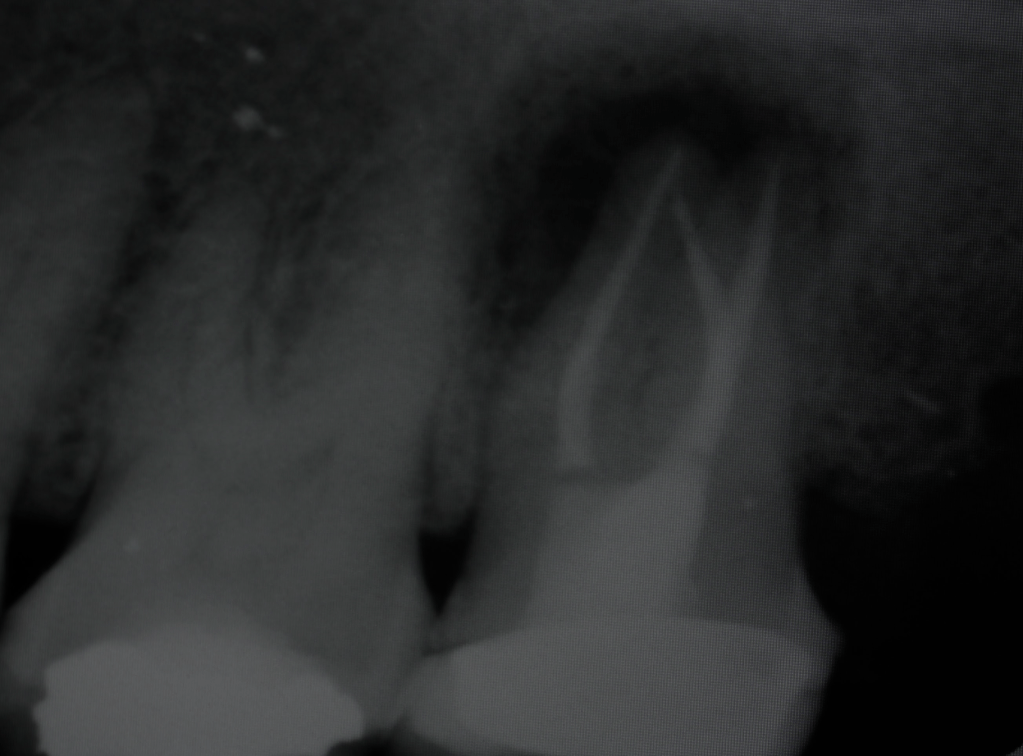

Fisura, remoción amalgama para explorar